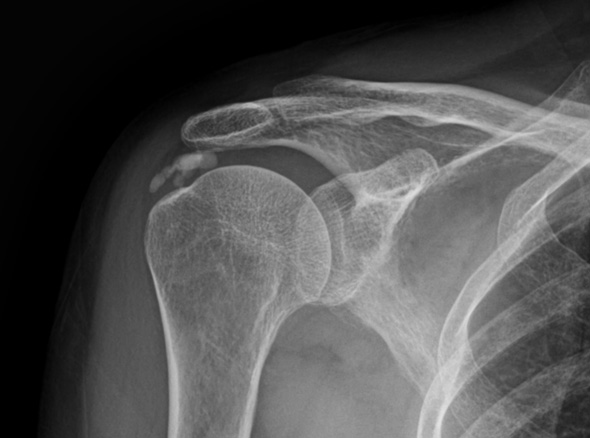

관절 내시경을 통한

석회제거술

내시경을 통하여 석회를 직접 보며,

힘줄 손상을 최소화시켜 석회 및 염증을 제거합니다.

이러한 경우

석회 제거술을

고려합니다.

수차례 충격파 치료 등에도 호전되지 않는 경우

주사 흡인술이 가능하지 않은 경우(오래되거나 딱딱한 석회)

1-2Cm 이상의 큰 석회

운동 범위의 감소가 매우 큰 경우

힘줄 파열이 동반되어 있는 경우